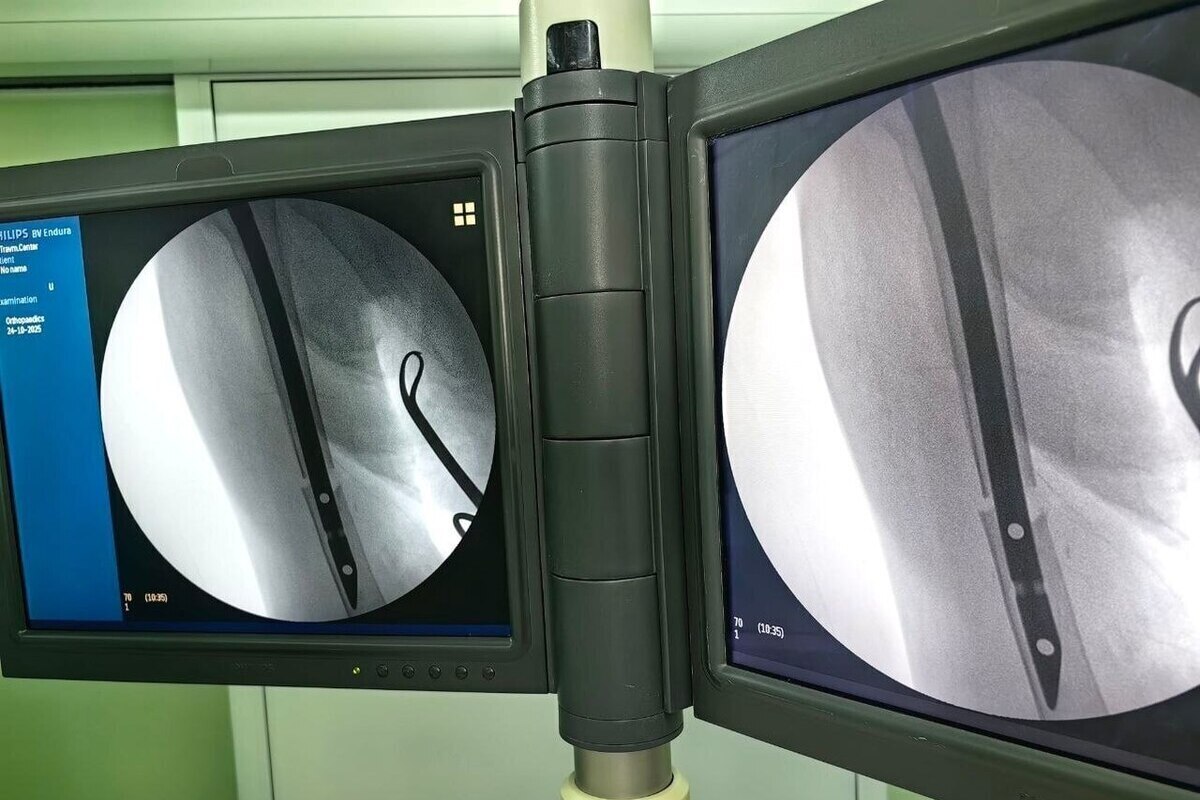

В сургутском травмцентре спасли пожилую пациентку с тяжёлой травмой — 92‑летняя женщина поступила в медучреждение с серьёзным переломом плеча. Как сообщили в пресс‑службе центра, консервативное лечение в этом случае могло спровоцировать опасные осложнения, поэтому медики приняли решение о хирургическом вмешательстве.

Врачи выполнили малоинвазивную операцию: в повреждённую кость установили специальный штифт. Такой метод позволяет минимизировать травматичность процедуры и ускорить восстановление пациента.

Проведённую операцию выполнил врач‑травматолог‑ортопед Артём Мещеряков. Он пояснил, что временный покой конечности необходим лишь в первые дни после хирургического вмешательства. По мере восстановления объём движений будет постепенно увеличиваться. Даже если организм не сможет полностью срастить перелом, рука сохранит работоспособность — это гарантирует установленный штифт.